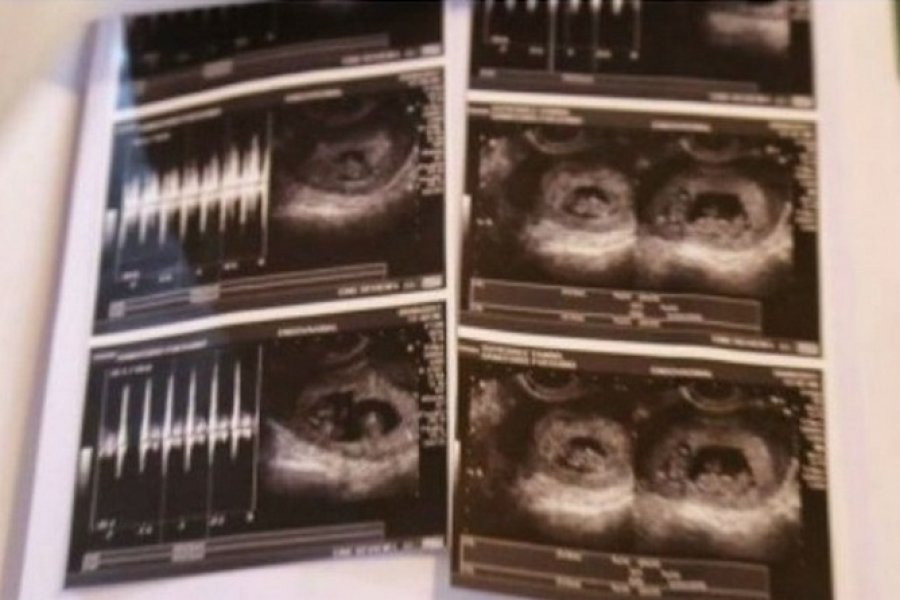

Una pareja de fueguinos tendrán mellizos y gemelos ¡a la vez!

De ser dos pasarán a ser seis en unos pocos meses. \"El médico no sabía cómo contarnos la noticia. Veíamos algo raro en la ecografía pero no entendíamos\", dijo la mujer.

Y, el médico me dijo: \'No, son más\'. ¡Trillizos!, pensamos nosotros y el doctor nos terminó confirmando: \'¡Son cuatro: en cada punta están los mellizos y en el medio los gemelos!\", relató la joven.

\"Son cuatro: En cada punta están los mellizos y en el medio los gemelos\", dijo el médico

TwitearSe trata de un embarazo múltiple y según ya les avisaron los médicos nacerán prematuros aproximadamente alrededor de los seis meses. Además, les recomendaron tenerlos en Buenos Aires porque en Tierra del Fuego los hospitales no están preparados para este tipo de partos.